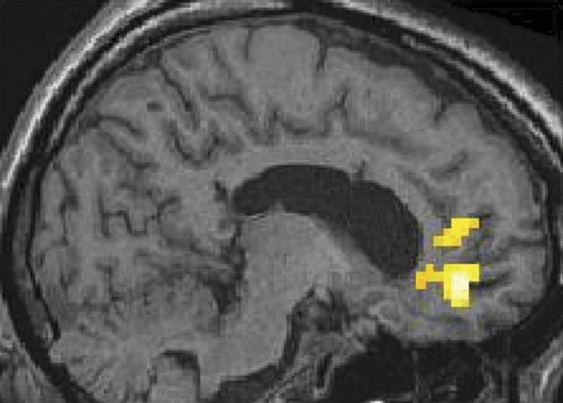

反应迟钝的清醒综合症患者应对别人的痛苦哭泣

在44个迟钝的失眠综合症患者使用fMRI,作者发现大脑的疼痛矩阵被喊痛的声音在其他激活,这表明患者认为自己经历了痛苦的人。情感意识可能仍在严重脑损伤患者没有认知的能力。

从作者Celesia & Sannita:“上述表明,我们可能需要更新的诊断和预后的指导方针,进行进一步的研究来定义和建立一个更可靠的VS(植物人)之间的界限和MCS最小意识状态。”